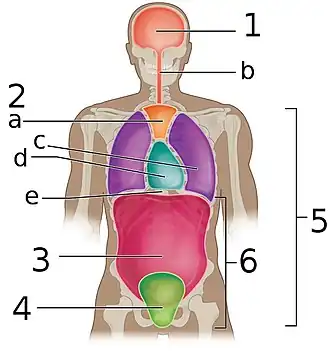

Frontal view of the body cavities: superior mediastinum labeled a, and the pericardial cavity, which is part of the inferior mediastinum, labeled d | |

The mediastinum (from Medieval Latin: mediastinus, lit. 'midway';[2]pl.: mediastina) is the central compartment of the thoracic cavity. Surrounded by loose connective tissue, it is a region that contains vital organs and structures within the thorax, mainly the heart and its vessels, the esophagus, the trachea, the vagus, phrenic and cardiac nerves, the thoracic duct, the thymus and the lymph nodes of the central chest.

The mediastinum can be divided into an upper (or superior) and lower (or inferior) part:

- The superior mediastinum starts at the superior thoracic aperture and ends at the thoracic plane.

- The inferior mediastinum from this level to the diaphragm. This lower part is subdivided into three regions, all relative to the pericardium – the anterior mediastinum being in front of the pericardium, the middle mediastinum contains the pericardium and its contents, and the posterior mediastinum being behind the pericardium.[6]